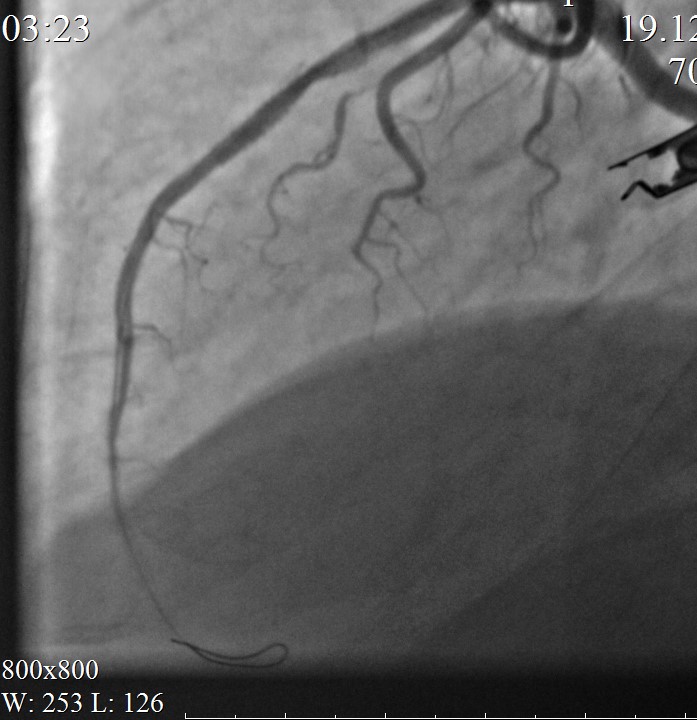

Выполнена имплантация стента-графта Aneugraft 3,5-27,0мм в стентированный сегмент (зону перфорации). Постдилатация.

Контрольная КАГ: успешное «пломбирование» разрыва. Кровоток по ПМЖВ TIMI III, в динамике без экстравазации.

Объективно: состояние пациента без ухудшения. Гемодинамика самостоятельная, АД 130/78 мм рт ст PS 80 в мин ЧДД 16 в мин. Жалоб не предъявляет.